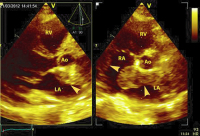

Echo

Abbildung 4: Parasternaler Längs- und Querschnitt: Darstellung der Raumforderung im linken und rechten Vorhof sowie im interatrialen Septum (Pfeile). LV: linker Ventrikel; LA: linker Vorhof; RV: rechter Ventrikel; Ao: Aorta